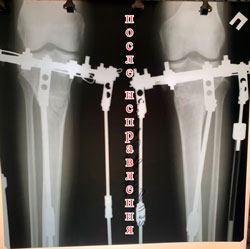

на фиксации

image-18-09-20-01-39-2.jpg

image-18-09-20-01-39.jpg